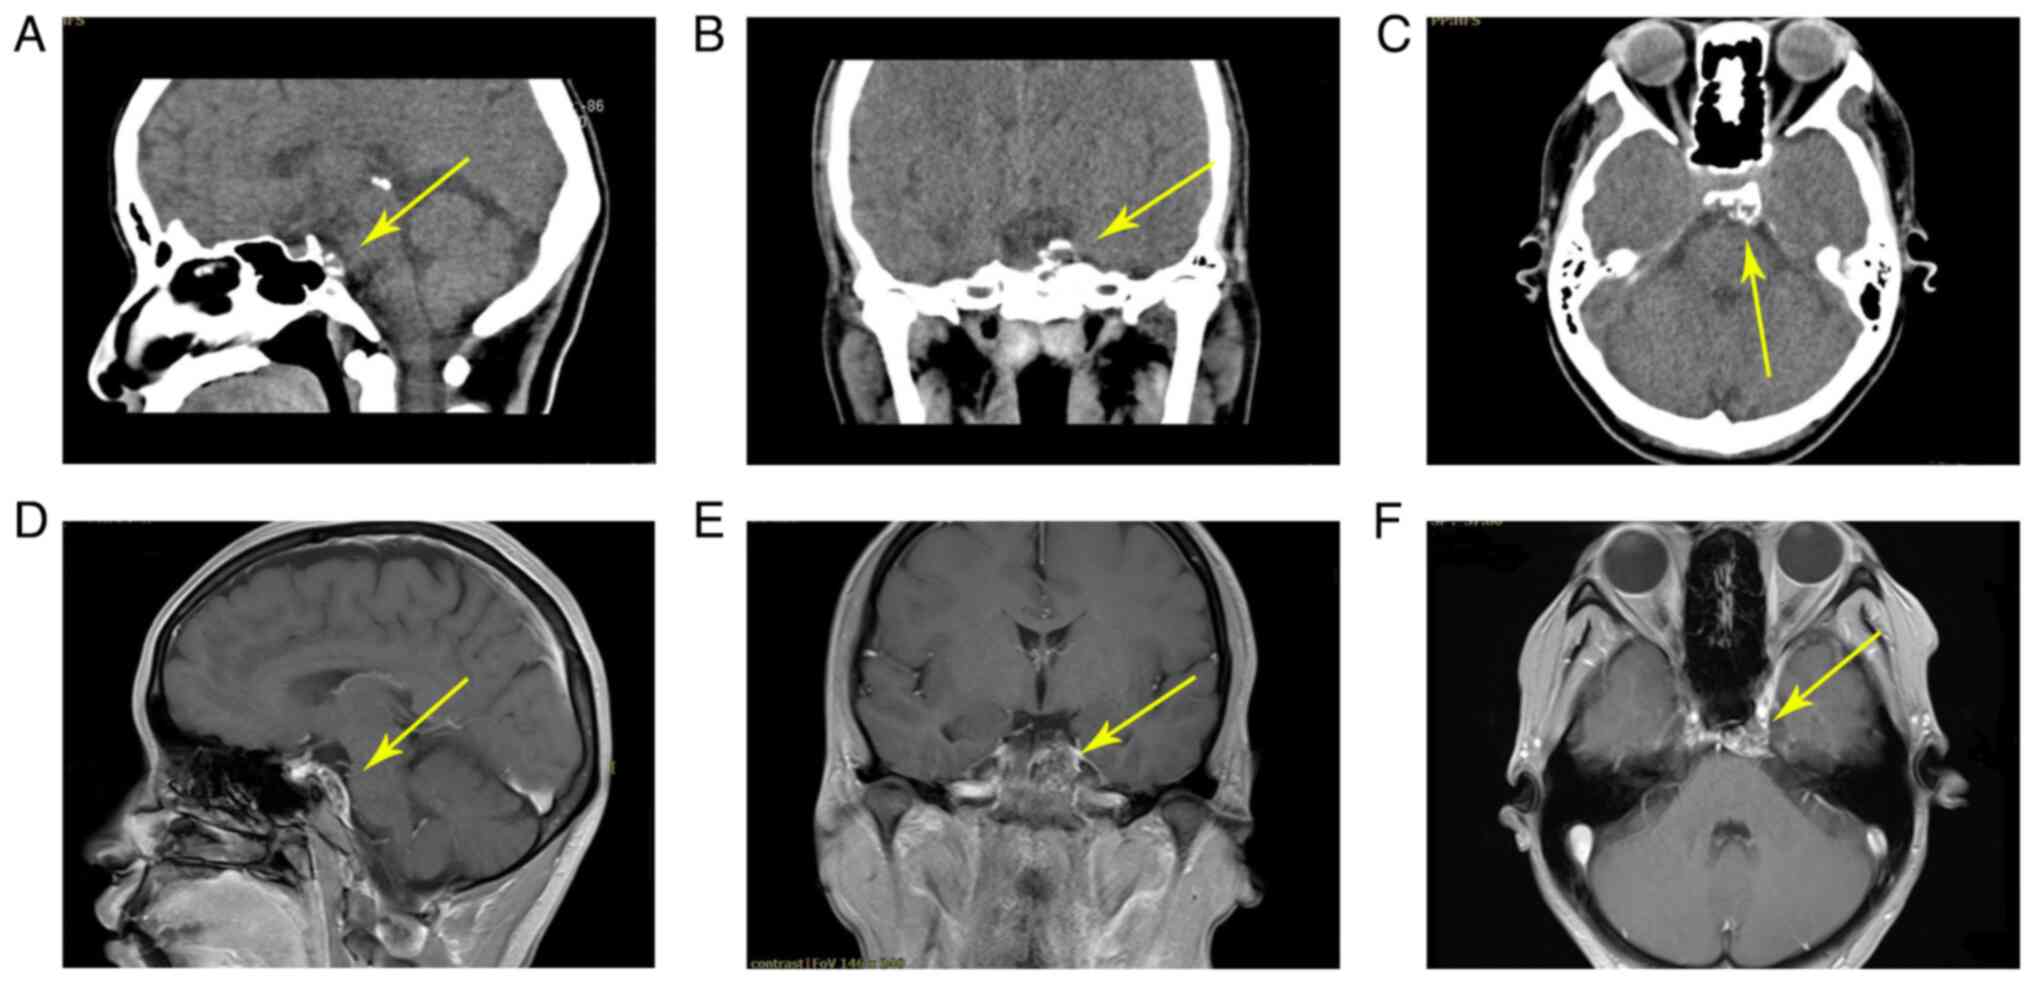

In November 2018, a 41-year-old female was admitted to Chongqing General Hospital (Chongqing, China) with esotropia of the left eye, visual impairment of the left nasal field and double vision for the previous 2 months. The patient received a comprehensive examination, including routine blood analyses and evaluations of liver, kidney, immune and blood coagulation functions, but all parameters were within the expected ranges. Neurological examination results were also as expected and there were no obvious signs of pathology. Furthermore, the patient had no history of trauma and no family history of hereditary illness. Visual acuity of the left eye was 0.8 and the extent of left eye esotropia was 10°, while the visual acuity and visual field of the right eye were normal. Preoperative CT scan images (Fig. 1A-C) demonstrated evidence of a calcified lesion with clear margins and enhancement in the left clivus region. This mass appeared hypo- or isointense on T1-weighted images (T1WI) and heterogeneously hyperintense on T2WI, with heterogeneous enhancement (Fig. 1D-F). The mass demonstrated swelling growth but did not break through the dura and there were no necrotic areas.

Figure 1.

Preoperative CT and MRI images. (A) Sagittal image of the preoperative CT. (B) Coronal image of the postoperative CT. (C) Axial image of the preoperative CT. The preoperative CT showed calcification with a clear margin and enhancement on the clivus. (D) Sagittal image of the preoperative MRI. (E) Coronal image of the postoperative MRI. (F) Axial image of the preoperative MRI. The MRI revealed a mass on the left side of the midline. Yellow arrows indicate the location of the lesion. CT, computed tomography; MRI, magnetic resonance imaging.